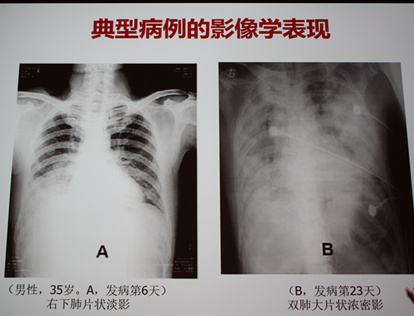

典型病例的影像学表现如图1。

图1